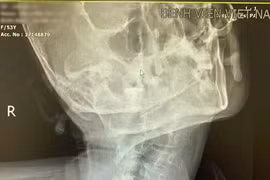

Người bệnh vẹo, xoắn cột sống cổ lâu năm là ca lâm sàng phức tạp do biến dạng giải phẫu vùng cổ làm tăng nguy cơ thất bại khi đặt nội khí quản thông thường.